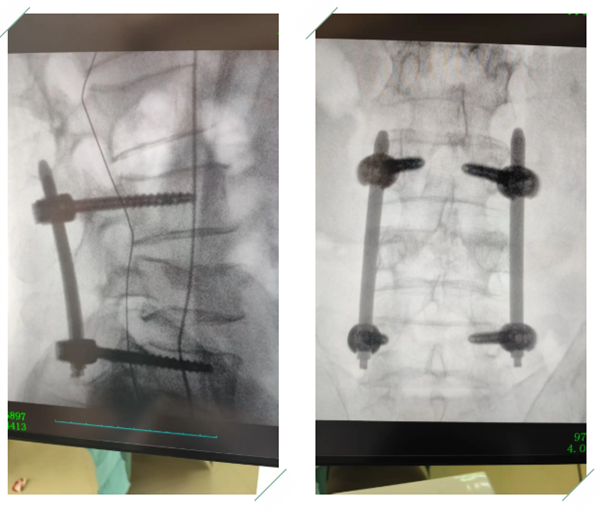

新春伊始,万象更新。在充满生机与希望的马年,南充市高坪区中医医院再添医疗新成果——医院党委副书记、院长、主任医师王飞带领骨科团队,成功完成马年首例腰4椎体骨折经皮复位椎弓根螺钉内固定术。此次手术的顺利开展,不仅展现了医院在脊柱外科领域的雄厚实力,也帮助患者重燃康复希望。

面对患者的病痛折磨与家属的殷切期盼,王飞院长第一时间组织骨科专家团队开展多学科会诊。专家组结合患者病情、身体状况,经严谨研讨、科学评估,一致确定腰4椎体骨折经皮复位椎弓根螺钉内固定术为最优治疗方案。该术式具有创伤小、出血少、恢复快、卧床时间短等显著优势,但对手术精度、医生专业技术水平要求极高。

手术当日,王飞院长带领手术团队提前就位,以高度负责的态度、严谨细致的作风做好术前准备。凭借多年深耕骨科领域的丰富临床经验,在C臂机精准定位引导下,王飞院长全神贯注、精准操作,精准将椎弓根螺钉置入预定位置。

手术过程中,团队成员分工协作、默契配合,每一个环节规范有序、每一项操作精准无误。历经紧张而高效的操作,手术圆满成功。当得知手术顺利完成的消息,患者家属难掩激动,连连向医护人员表达感激之情。